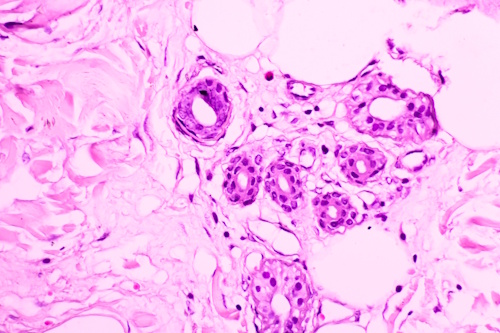

Как выглядят раковые клетки под микроскопом?

Раковые клетки под микроскопомЕсли раковую клетку рассмотреть под микроскопом, можно заметить ее неправильную форму. Визуализируется аномально крупное ядро, содержащее много ДНК. Здоровые клетки, взятые из одного участка ткани, похожи между собой. Клетки злокачественных опухолей отличаются друг от друга.

Бесконтрольное деление приводит к тому, что клетки располагаются более хаотично. Им легко проникнуть в соседние органы через кровеносную систему.